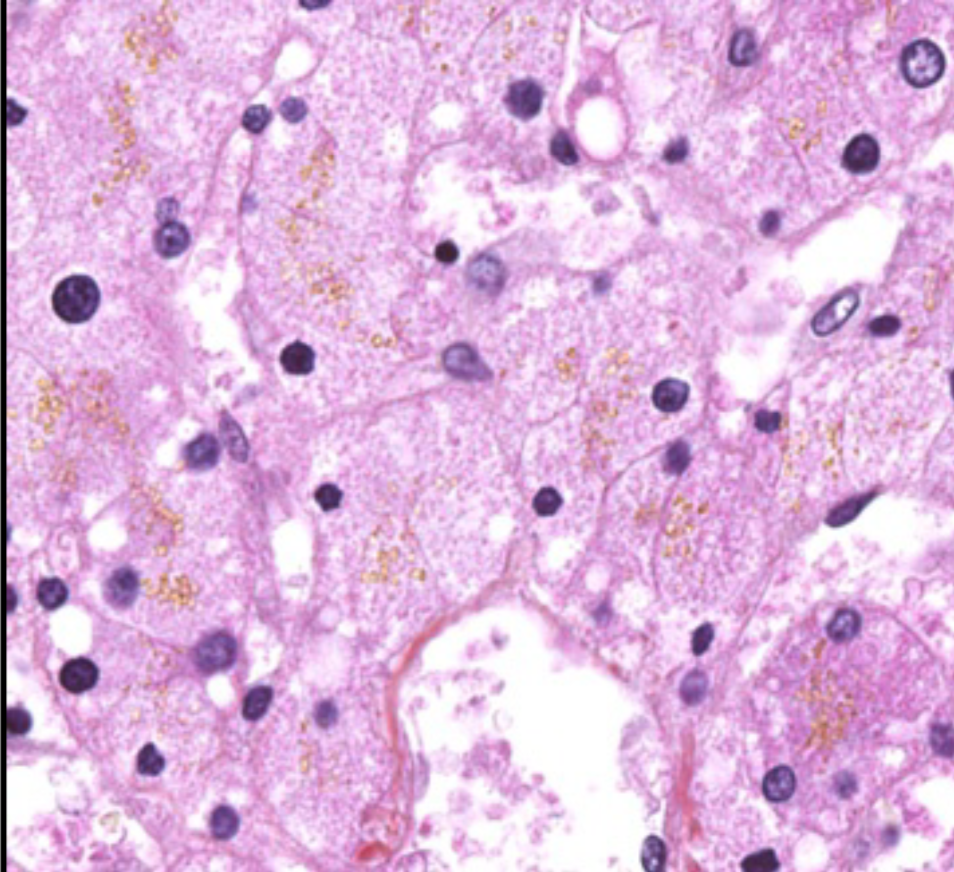

hémosidérose rénale